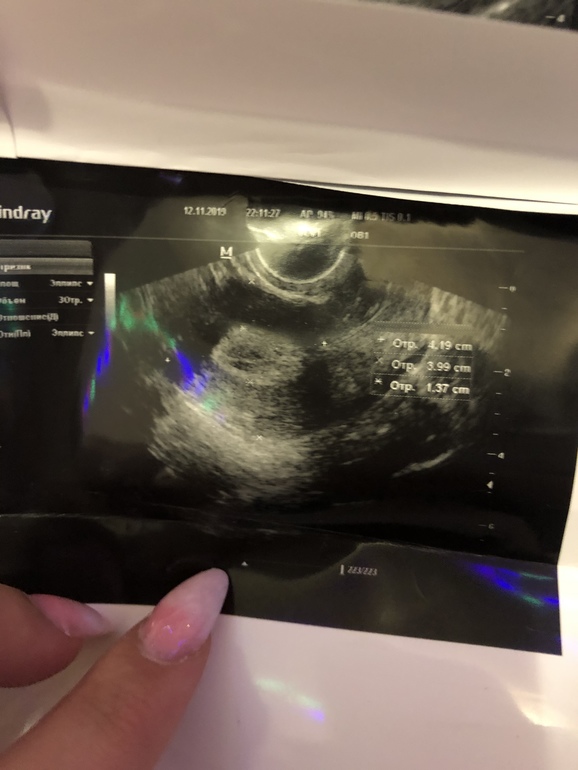

Задержка сегодня уже 20 дней

Делала узи примерно 5 ноября (сказали что овуляция успешно прошла и готова к беременности)

Потом пришла 12 ноября, меня напугали что возможна внематочная беременность, направили делать тест хгч, но результатов ещё нет, да и боюсь, что может врач сделает ошибку.

Скажите, пожалуйста,

если кто знает, нормальное ли узи и что оно означает

Заключение УЗИ где? Мы тут глазами вашего врача посмотреть на фото не можем🤷♀️

Размер эндометрия? Наличие жёлтого тела в яичнике?

По узи от 5 ноября овуляция когда прошла? За пару дней до 5 ноября или за две недели? Если за пару дней, то примерно сейчас у вас 15 дпо и никакой задержки в 20 дней. Если за две недели уже другой разговор.

А где заключение? По снимку тут никто ничего не скажет. На момент УЗИ желтое тело было? У меня тоже 11 дней задержки. Хгч и узи отрицательные